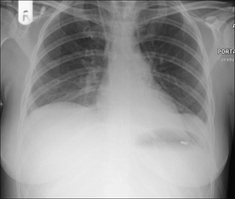

Figure 28.1 Chronic dyspnoea. Extensive alveolar shadowing. Wide differential diagnosis. Apply Golden Rule 1—clinical details are crucial. Known renal failure with fluid retention. CXR conclusion—alveolar pulmonary oedema.